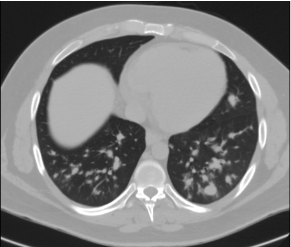

A 26-year-old male with chronic sinusitis presented to clinic for evaluation of nasal crusting and bloody discharge (Image 1). He had a history of nasal polyposis resection. Laboratory evaluation was significant for leukocytosis and mild anemia. CXR showed nonspecific multifocal patchy infiltrates. Chest CT revealed numerous bilateral pulmonary nodules with central cavitation (Image 2). Immunological testing revealed the presence of c-ANCA and proteinase 3 (PR3) antibodies. GPA was suspected and the patient was started on prednisone. Bronchoscopy showed friable nasal mucosa with cobble stoning. Infectious workup was negative. He was initiated on high dose steroid with a plan to add rituximab (RTX). Few days later, he presented with chest pain, he was hypertensive and tachycardiac, he had elevated BNP and troponin. EKG showed no ST changes, but Echocardiogram revealed an EF of 50% with dilated left ventricle. Coronary vasculitis was suspected, cyclophosphamide (CYC) induction was initiated. Cardiac MRI demonstrated moderate systolic dysfunction with EF 34% and atypical myocarditis. Left heart catheterization (LHC) revealed disseminated vasculitis with diffuse involvement of distal coronary arteries. He was initiated on guideline-directed medical therpay and given RTX. A week later, he presented with elevated creatinine. Renal biopsy revealed ANCA-mediated focal crescentic glomerulonephritis. He underwent plasmapheresis with imporvement of his kidney function. A month later, he presented with recurrence of chest pain. Troponins were elevated, EKG demonstrated inferior ST elevation, and LHC revealed progression of coronary vasculitis. Repeat echocardiogram showed an EF of 15%. He was treated with steroids, and CYC. However, he continued to worsen, and eventually progressed to cardiogenic shock with multiorgan failure and was put on VA-ECMO support. The patient was transferred to a higher level of care center for LVAD and heart transplant.